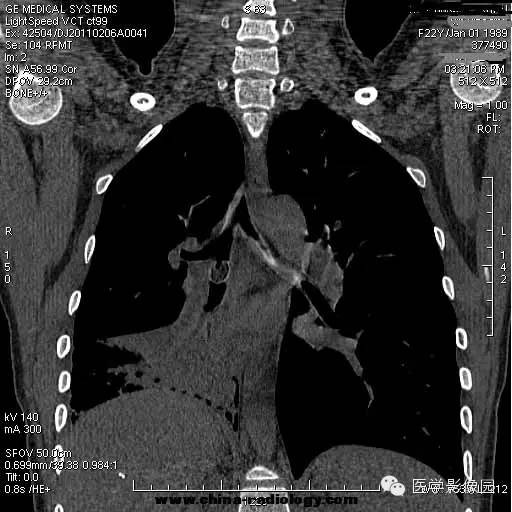

【病例】支气管异物1例CT影像表现

女,22岁,食用开心果后咳嗽不适。

管支气管异物是临床常见急症。异物可存留在喉咽腔、喉腔、气管和支气管内,引起声嘶、呼吸困难等,右支气管较粗短长,故异物易落入右主支气管。75%发生于2岁以下的儿童。CT三维重建清晰直观的显示异物的大小、位置,并能观察肺组织内是否有病变。